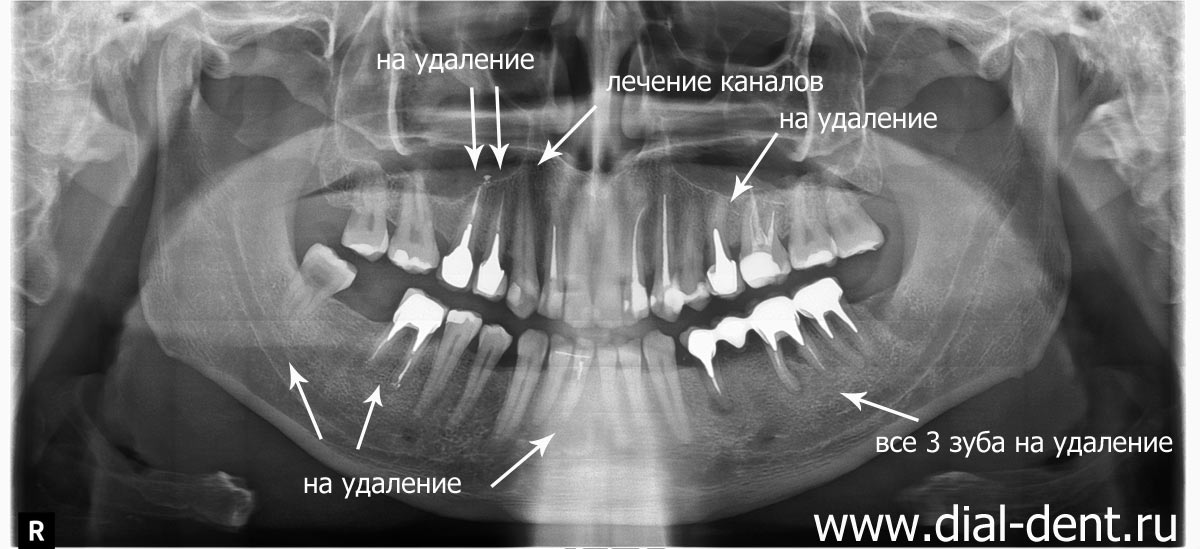

Фотографии и схемы для ОПТГ и мезиального прикуса